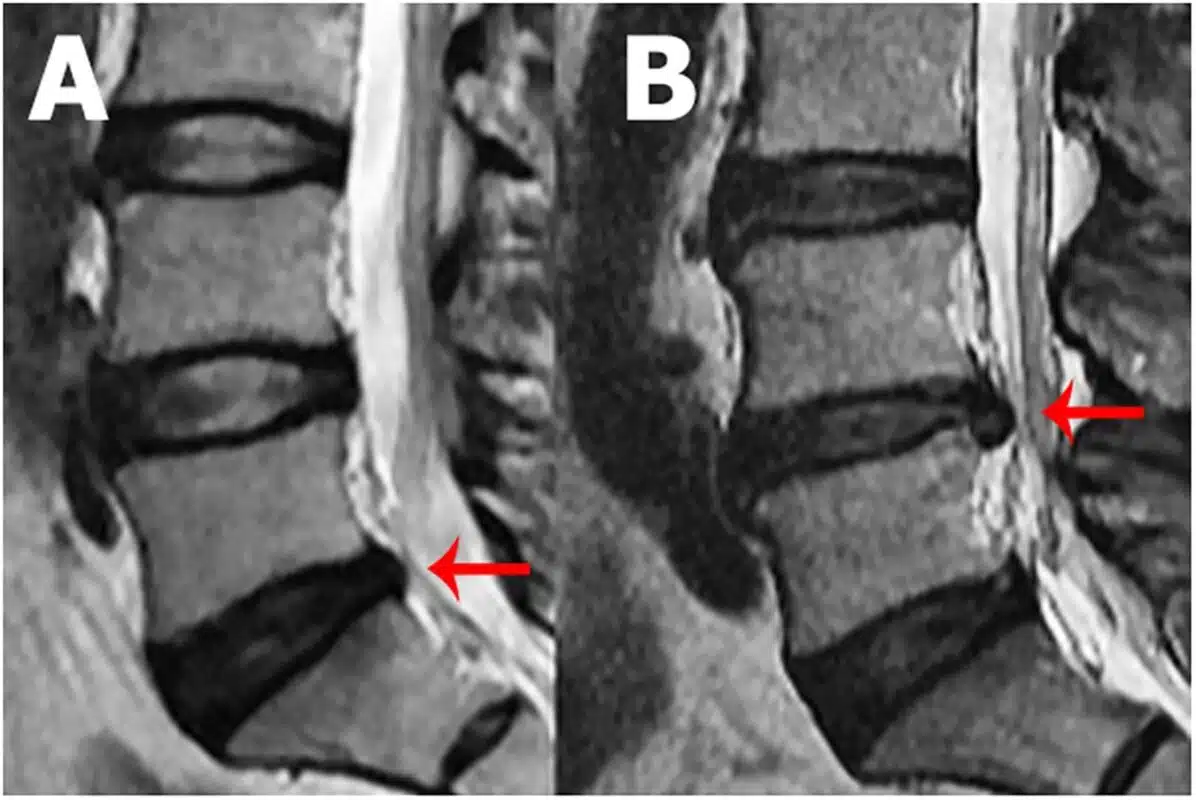

If you decide to see a chiropractor, it’s important to choose a qualified and licensed practitioner who has experience in treating disc-related issues. They should conduct a thorough evaluation of your condition and take into account your medical history and any previous diagnostic imaging, such as MRI scans, to ensure they can provide appropriate care and avoid potentially exacerbating your condition.